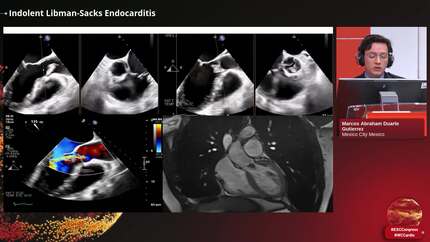

A Hidden Culprit: Unrevealed Aortic Valve Endocarditis Complicated by Inferior ST-Elevation Myocardial Infarction